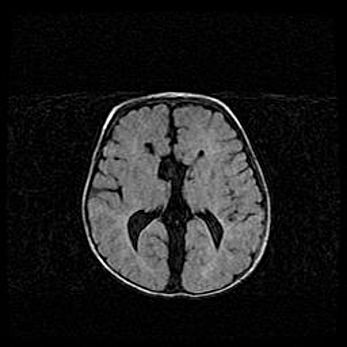

Неполная лизэнцефалия (пахигирия). Открытая гидроцефалия.

Возраст: 17 дней

Вес: 3110 г

Пол: мужской

Окружность головы: 33,5 см

Срок гестации: 35-36 недель

Лизэнцефалия—недоразвитие корковой пластинки и мозговых извилин в результате нарушения миграции нейронов коры. Поверхность мозговых полушарий гладкая. Микроскопически выявляется отсутствие нормальных слоев коры и скопление групп нейронов в подкорковом белом веществе.

Пахигирия—уменьшение числа вторичных извилин. В пораженном полушарии нервные клетки образуют толстый недифференцированный слой с неправильно расположенными нервными волокнами и группами гетеротопных клеток. Нервные клетки незрелые. Белое вещество истончено. При этом нередко аномально развит корково-спинномозговой путь.